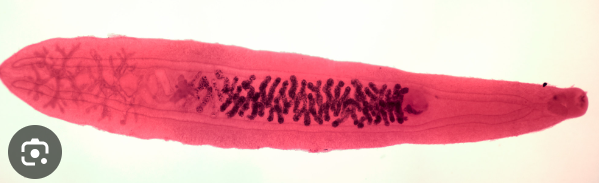

lupa

Clonorchis sinensis - marita